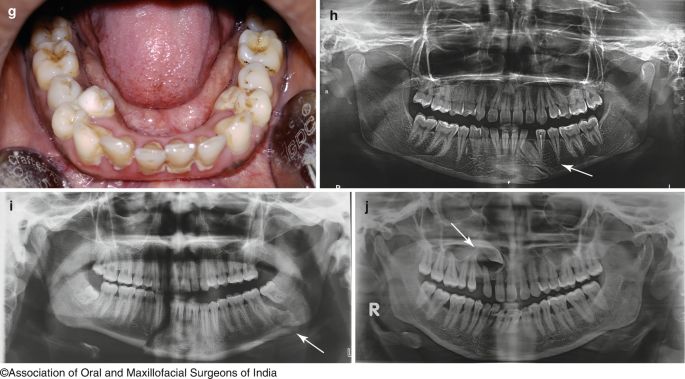

Tian z Hangzhou, podobnie jak wielu jego rówieśników, doświadcza nietypowego zjawiska w rozwoju zębów. W wieku, kiedy dzieci zwykle tracą mleczaki, siedmiolatek zamiast zastąpienia ich stałymi zębami, zaskoczył rodziców i lekarzy. Zamiast dwóch, wyrastały mu cztery zęby na jednym miejscu. Zjawisko "podwójnych zębów" staje się coraz bardziej powszechne i budzi zaniepokojenie specjalistów.

Lekarze zwracają uwagę, że problem może być związany z nawykami żywieniowymi współczesnych dzieci. Jak czytamy w portalu branżowym CzytelniaMedyczna.pl, gryzienie twardych pokarmów, takich jak surowe owoce czy warzywa, ustępuje miejsca łatwiejszym w spożyciu formom, np. sokom czy smoothie. To kwestia wygody, ale ta zmiana ma swoje konsekwencje dla rozwoju zębów dzieci.

Zgodnie z zaleceniami specjalistów, kluczowe jest, aby rodzice od najmłodszych lat przyzwyczajali dzieci do żucia. To nie tylko kształtuje prawidłową funkcję zębów, ale także wspiera ich zdrowy rozwój. Samodzielne gryzienie pomaga w prawidłowej wymianie mleczaków na zęby stałe oraz zapobiega problemom takim jak "podwójne zęby".

Stomatolodzy podkreślają, że nowe stałe zęby mogą wyglądać na postrzępione, co jest zjawiskiem naturalnym. Wynika to z procesu ich rozwoju, który może obejmować ograniczoną przestrzeń, jaką pozostawiają po sobie mleczne zęby, co dodatkowo komplikuje proces ich zastępowania.